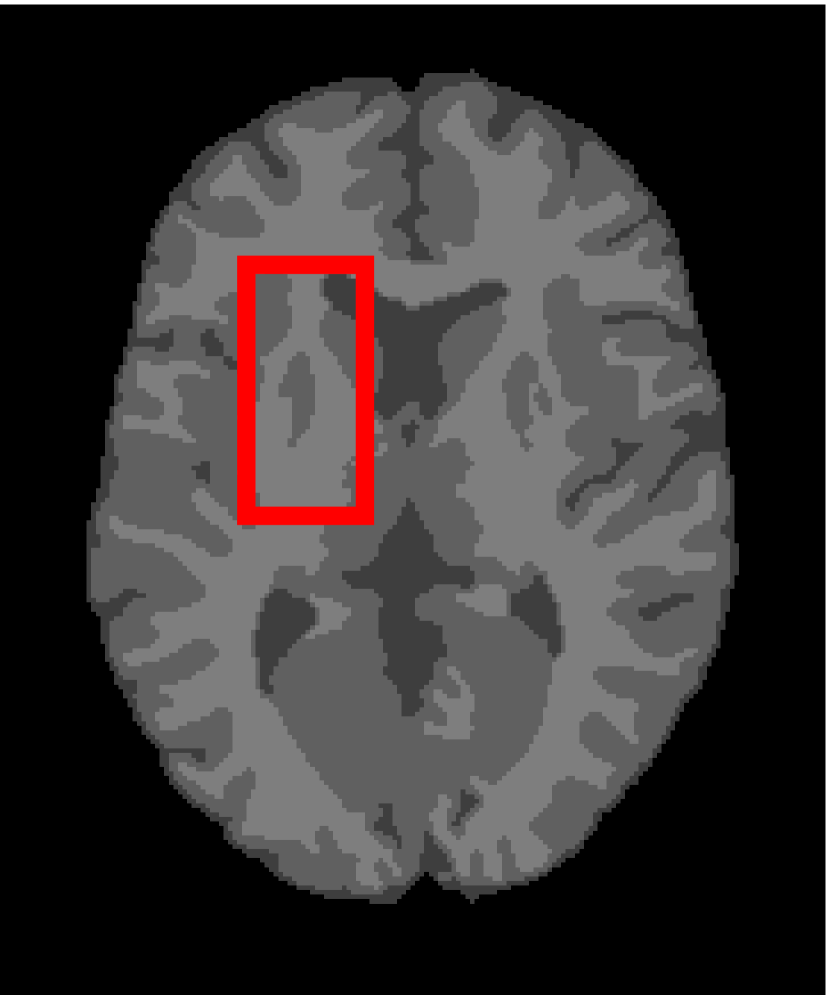

Next, we representatively segment five medical images from BrianWeb. They are represented as five slices in the axial plane with a sequence of 70, 80, 90, 100 and 110, which are generated by T1 modality with slice thickness of 1mm resolution, 9% noise and 20% intensity non-uniformity. Here, we set c=4𝑐4c=4 for all cases. The comparison between WRFCM and its peers are shown in Fig. 9 and Table II. The best values are in bold.

Figure 9: Segmentation results on five medical images. The parameter: ϕ=5.35italic-ϕ5.35\phi=5.35. From top to bottom: noisy images, ground truth, and results of FCM_S1, FCM_S2, FLICM, KWFLICM, FRFCM, WFCM, DSFCM_N, and WRFCM.

By a view of the marked red square in Fig. 9, we find that FCM_S1, FCM_S2, FLICM, KWFLICM and DSFCM_N are vulnerable to noise and intensity non-uniformity. They give rise to the change of topological shapes to some extent. Unlike them, FRFCM and WFCM achieve sufficient noise removal. However, they produce overly smooth contours. Compared with its seven peers, WRFCM can not only suppress noise adequately but also acquire accurate contours. Moreover, it yields the visual result closer to ground truth than its peers. As Table II shows, WRFCM obtains optimal SA, SDS and MCC results for all five medical images. As a conclusion, it outperforms its peers visually and quantitatively.